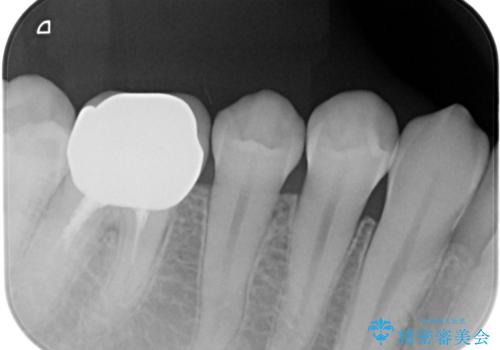

被せ物だけの治療を選択されましたのでジルコニアクラウンでの治療を行いました。

適合の良い被せ物が入りました。